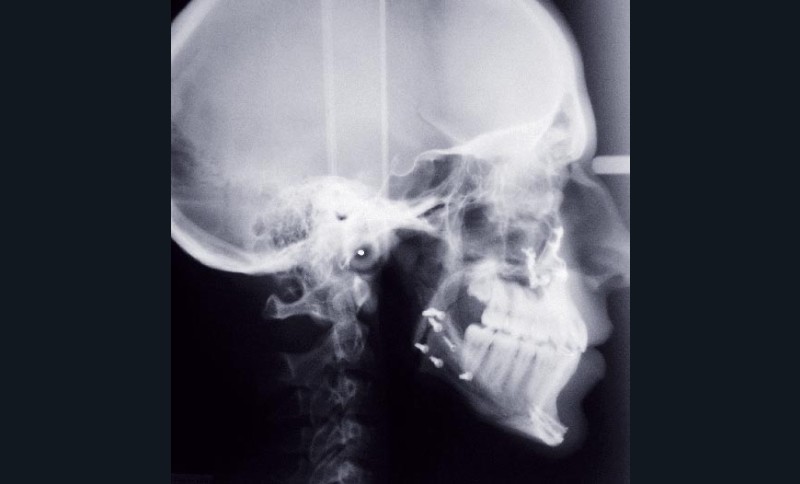

Olivier se présente à l’âge de 12 ans avec une classe III squelettique à prédominance mandibulaire, accompagnée d’une hyperdivergence et d’une endomaxillie responsable des inclusions des canines supérieures à forte obliquité. Une phase d’expansion est réalisée afin de permettre une augmentation du périmètre de l’arcade et la verticalisation des germes des canines. L’expansion permet en effet une normalisation transversale mais ne permet pas de réaliser la mise en place des canines. Les extractions des prémolaires sont alors effectuées et une préparation primaire de l’arcade supérieure par multi-attaches avec désinclusions et tractions des canines est réalisée.

Une pause thérapeutique est ensuite entamée jusqu’à la fin de croissance soit 18 ans. Une poursuite du traitement par préparation secondaire à la chirurgie orthognathique bimaxillaire est programmée.

Les mouvements de décompensations sagittales et transversales sont réalisés à l’aide des tractions inter-arcades. La réévaluation céphalométrique et l’analyse des moulages confirment l’indication d’une chirurgie maxillaire de propulsion et d’une chirurgie mandibulaire par clivage bilatéral des branches montantes pour un recul mandibulaire modéré accompagné d’une génioplastie bidimensionnelle élargie qui rappelle la technique de Chin Wing.